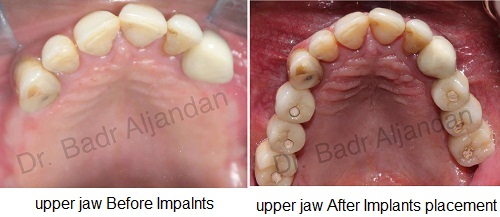

SURGICAL PROCEDURE

For most patients, the placement of dental implants involves two surgical procedures. First, implants are placed within your jawbone. For the first three to six months following surgery, the implants are beneath the surface of the gums gradually bonding with the jawbone. You should be able to wear temporary dentures and eat a soft diet during this time. At the same time, your dentist is forming new replacement teeth.

After the implant has bonded to the jawbone, the second phase begins. Dr. Al-jandan will uncover the implants and attach small posts that protrude through the gums and will act as anchors for the artificial teeth. When the artificial teeth are placed, these posts will not be seen. The entire procedure usually takes six to eight months. Most patients experience minimal disruption in their daily life.

A single prosthesis (crown) is used to replace one missing tooth – each prosthetic tooth attaches to its own implant. A partial prosthesis (fixed bridge) can replace two or more teeth and may require only two or three implants. A complete dental prosthesis (fixed bridge) replaces all the teeth in your upper or lower jaw. The number of implants varies depending upon which type of complete prosthesis (removable or fixed) is recommended. A removable prosthesis (over denture) attaches to a bar or ball in socket attachments, whereas a fixed prosthesis is permanent and removable only by the dentist.